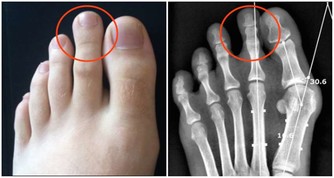

但是醫學研究發現痛風產生的尿酸結石等病變早期主要影響腎小管的重吸收功能,使人體濃縮尿液的能力下降,這是在悄無聲息損傷痛風患者的腎臟,而且並不一定會反應為血肌酐升高。所以,在腎內科一般都認為痛風都會百分百引發腎臟損害!